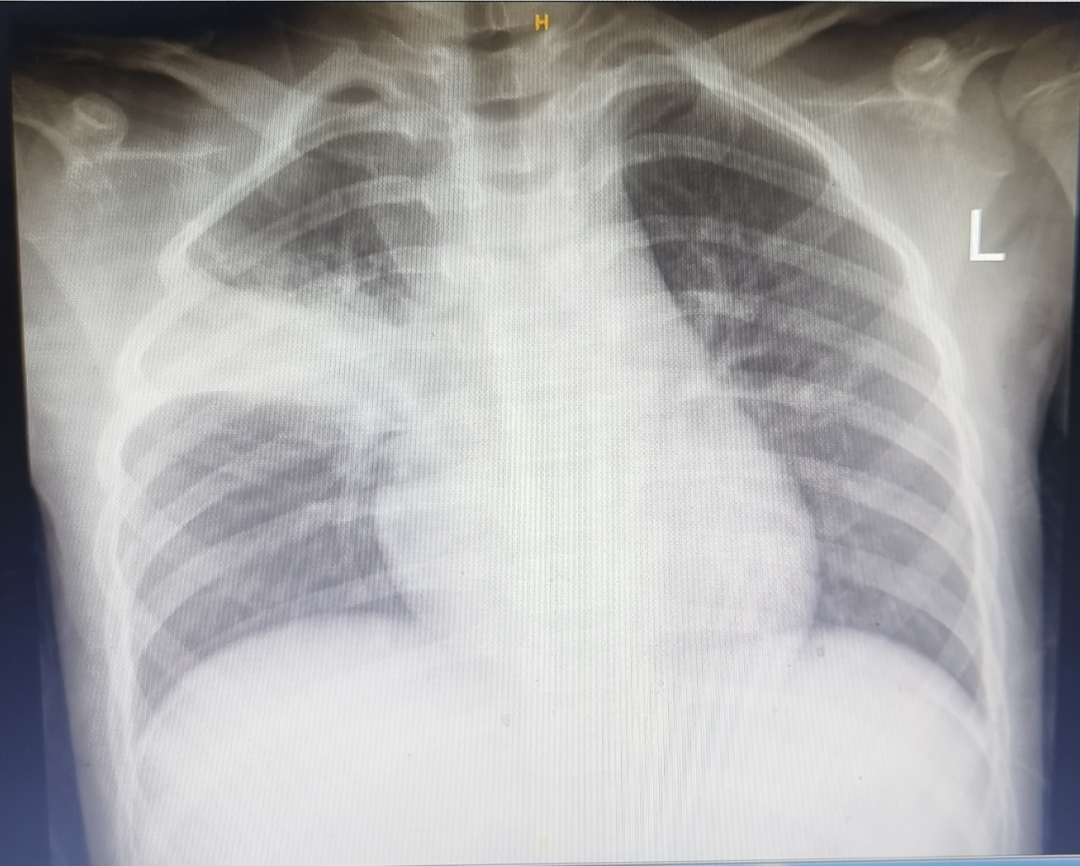

图片

部分家长就诊时第一句话就是:“医生赶紧给我们拍个片看看,是不是白肺了?”其实,肺炎支原体肺炎在影像学上表现为大片状肺炎,也可能合并肺不张、胸腔积液等。但是和双肺弥漫性病变的”白肺”是两个概念。通常也不建议病程1-2天即行影像学检查,还是要结合病情判断。